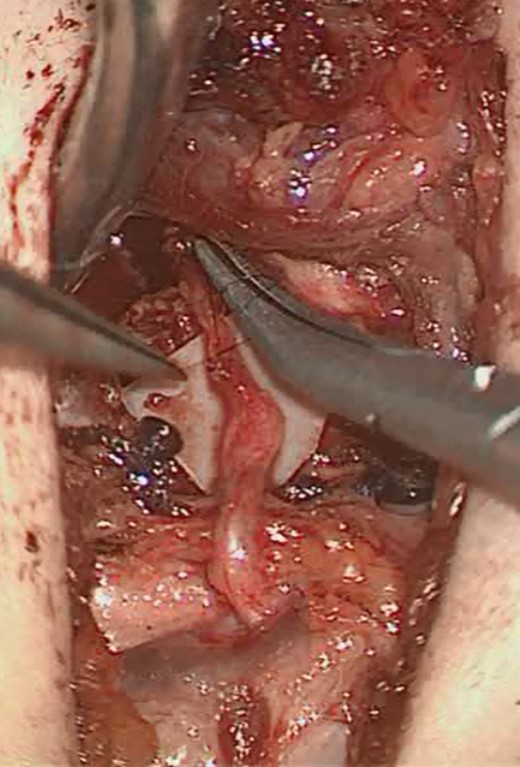

Approximated left ansa cervicalis branch and left recurrent laryngeal nerve (RLN).

A left horizontal neck crease incision at the level of the cricoid was performed. After identification of the internal jugular vein and carotid artery, a branch of the ansa cervicalis was identified, preserved and freed superiorly. The RLN was identified in the tracheoesophageal groove; the left ansa cervicalis branch was divided, trimmed and anastomosed to the divided and trimmed RLN using 10.0 Ethilon sutures and the operating microscope, fibrin glue was used to surround the anastomosis.